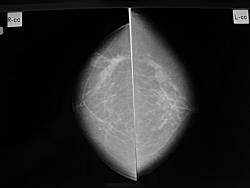

1958 г.р. кожа и соски без патологических изменений. https://radiomed.ru/sites/default/files/styles/case_slider_image/public/user/1787/dsc01253.jpg?itok=TFWCh-Xo ID:55041 Пт, 28/01/2011 - 18:46 #1 Аризона Не на сайте Был на сайте: 3 года 1 месяц назад Зарегистрирован: 03.02.2010 - 17:17 Публикации: 109 справа в в/н. квадранте очень подозрительная деформация стромы, a слева у субмаммарной складки все таки на коже чего есть Сб, 29/01/2011 - 05:59 #2 Vikkur Не на сайте Был на сайте: 4 года 8 месяцев назад Зарегистрирован: 24.09.2009 - 14:34 Публикации: 1749 Спасибо за комент - 100% попадание.. Виктор.

справа в в/н. квадранте очень подозрительная деформация стромы, a слева у субмаммарной складки все таки на коже чего есть